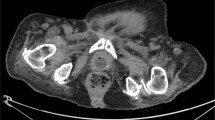

Case report: A 25-year-old man sustained complete SCI at C6 level following a road traffic accident. After 14 months, while on self-intermittent catheterization he noticed difficulty in introducing catheter and acute retention of urine. X-ray examination revealed a calculus in the penile urethra at the level of the glans penis.

Conclusion: Impaction of calculi in penile urethra, although rare, can manifest with acute painless urinary retention in patients with SCI.